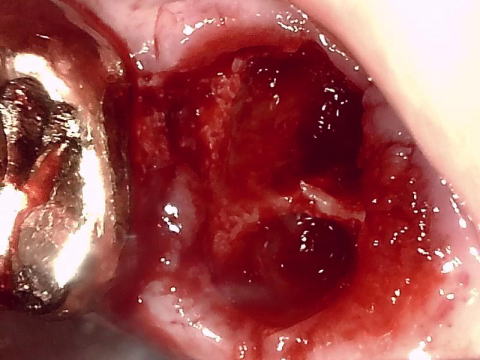

■ 抜歯直後像(内視鏡)

-HIGH RESOLUTION DIGITAL CAMERA-

(CMOS:92万画素、LED5照明)